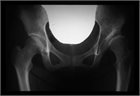

1. 寛骨臼の形成不全により、関節の安定性が障害された状態を寛骨臼(臼蓋)形成不全(acetabular dysplasia)という。

1. 寛骨臼(臼蓋)形成不全は小児から高齢者までに認められ、変形性股関節症のリスク因子である(推奨度1)

1. 股関節単純X線像で寛骨臼(臼蓋)形成不全があり、股関節痛がある場合は、専門医へ紹介する(推奨度1)